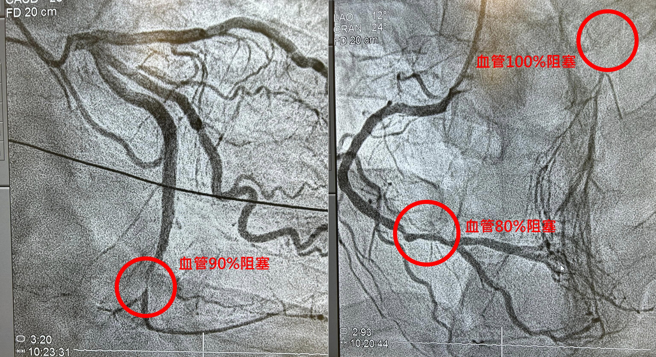

医师陈冠任在脸书粉专「冠任医师的异想世界」分享个案,一名41岁男子在健身房突发心因性猝死,当场无呼吸心跳,所幸在旁人急救下才恢復意识,检查发现男子心臟三条血管堵塞严重,最重要的一条干道100%完全阻塞,其他两条血管也有80%、90%堵塞状况。

男子清醒后自述不菸不酒、无不良嗜好或是高血压糖尿病,甚至定期运动,不解为何才40岁就有严重的血管栓塞,陈冠任检视男子去年健检报告后,也发现导致心因性猝死的关键原因。

陈冠任表示,原来男子体内「好胆固醇(高密度脂蛋白)HDL」过低,「坏胆固醇(低密度脂蛋白)LDL」又异常的高,长年下来导致血管退化狭窄,三条血路都坑坑疤疤藕断丝连,后续只能做绕道手术或放支架,才能拆除体内的不定时炸弹。